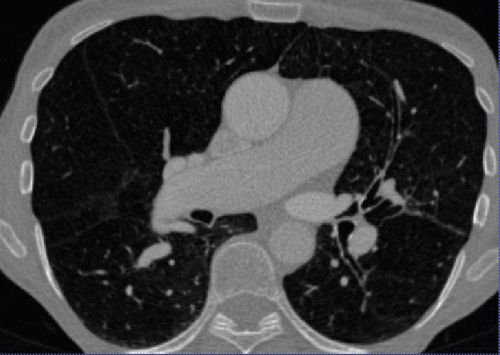

We found a correlation between DM and mPAP of (Spearman correlation coefficient, p<0.01). There was a significant difference between the DM of patients with and without PH (Table 2, p<0.05), thus enabling to discriminate the two groups on our dataset of 24 patients. Two representative vessel segmentation results of the PH study datasets are shown in Figure 7.